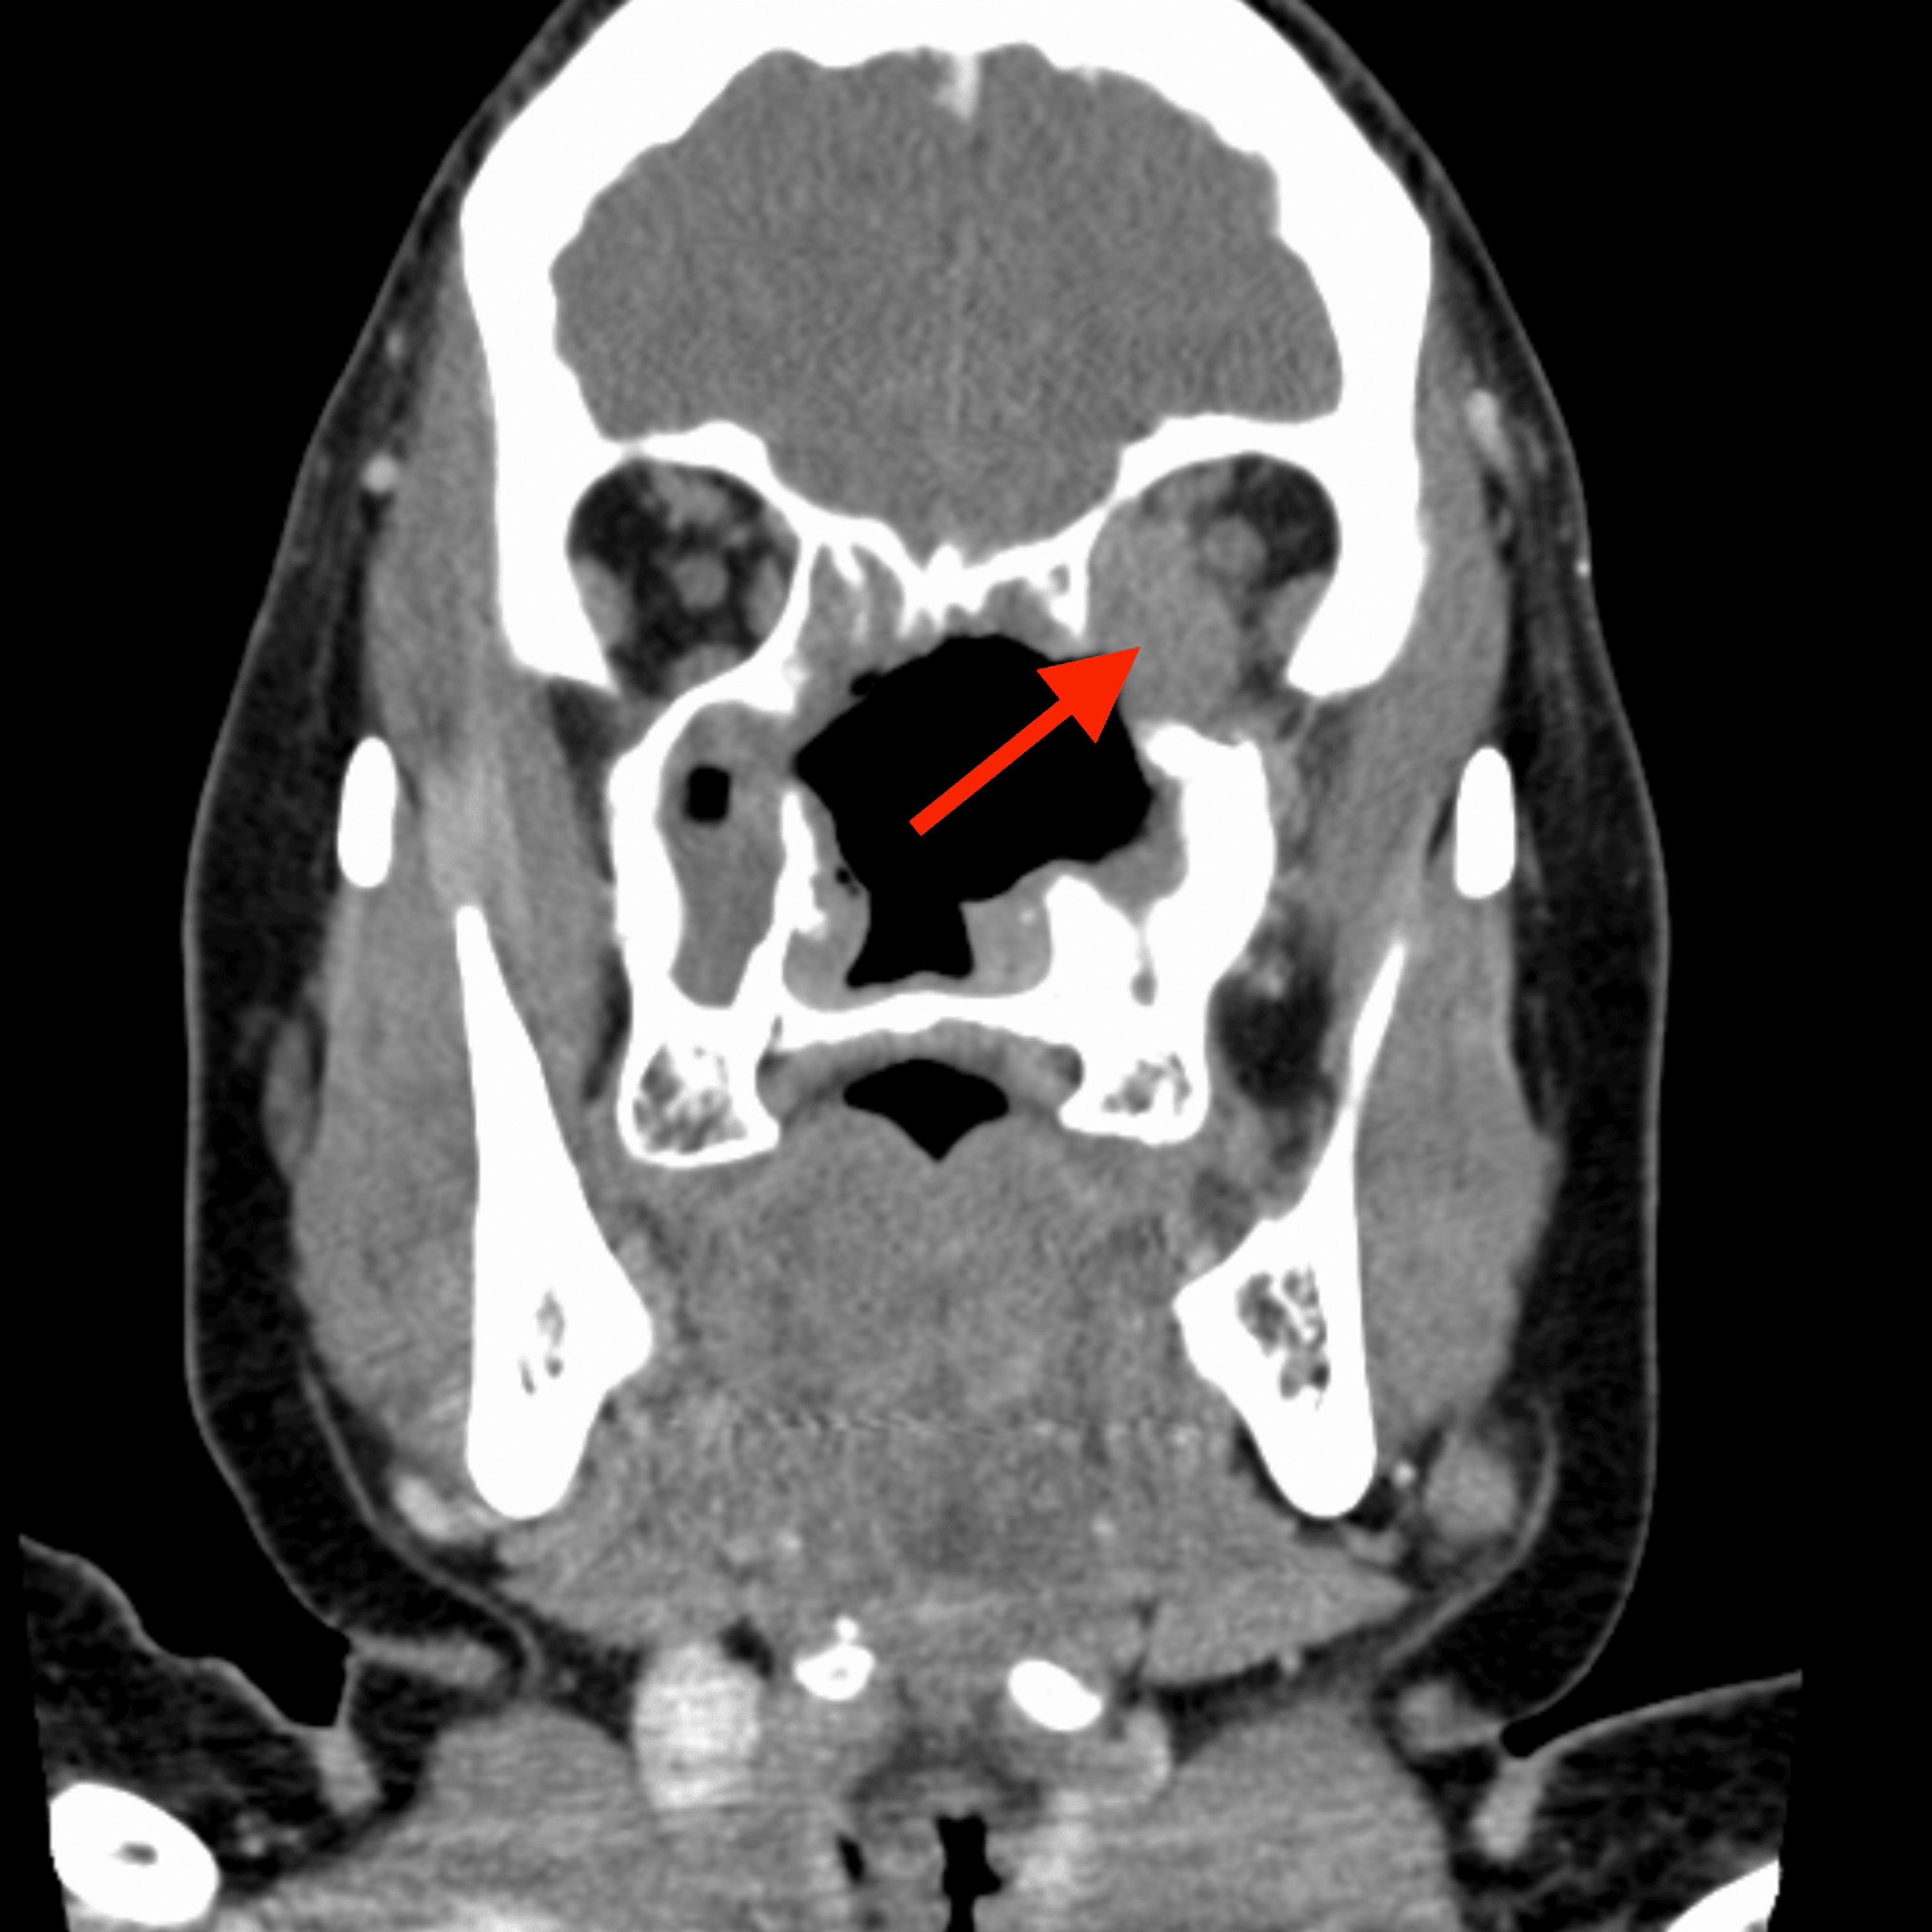

Coronal computed tomography image through the face (bone windows) The BMJ Facial Bones With Contrast Ct Ct orbits (computed tomography of the orbits) involves the visualization of bony and soft tissue structures of the orbits. What is a ct of the head, orbits, sinuses or facial bones and what does it do? A ct of the head is an exam that takes very thin slice images of the. The labeled structures are (excluding the correct side):. Facial Bones With Contrast Ct.